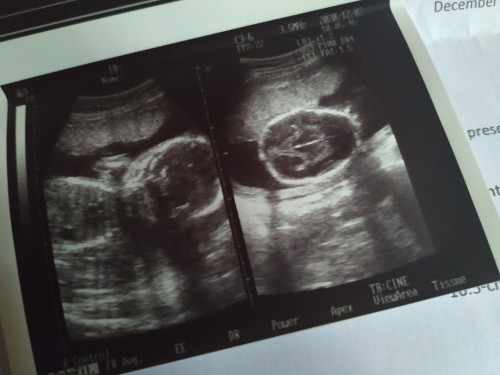

23 weeks pregnant.

23 weeks pregnant po ako . at nagpaultrasound po ako at sabi ng nag ultrasound sakin na suhi pa daw si baby.. Iikot po ba si baby ? I mean kilan kaya pwede magpa uktrasound uli pra malaman kung suhi pa ba si baby#pregnancy #firstbaby